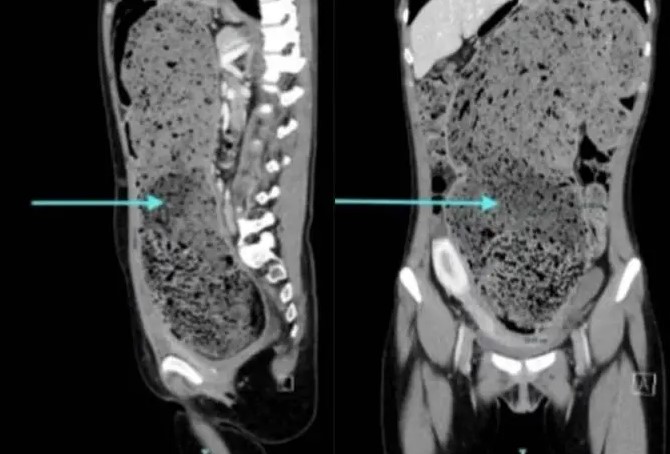

Uma tomografia computadorizada confirmou a gravidade do quadro ao mostrar que o intestino da jovem estava completamente obstruído por fezes acumuladas. A equipe médica também identificou um cólon sigmoide redundante, estrutura anatomicamente mais longa que o habitual, com 15 cm de diâmetro, o que favorece episódios persistentes de constipação.